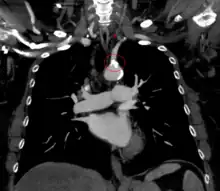

| The proximal part of left subclavian is blocked (shaded artery). This prevents antegrade ("forward") flow to the left arm and left vertebral. As a result, flow in the left vertebral is retrograde ("backwards") towards the left arm. Flow to the brain and circle of Willis is via antegrade right and left carotid and right vertebral arteries. | |

Subclavian steal syndrome (SSS), also called subclavian steal steno-occlusive disease, is a constellation of signs and symptoms that arise from retrograde (reversed) blood flow in the vertebral artery or the internal thoracic artery, due to a proximal stenosis (narrowing) and/or occlusion of the subclavian artery. This flow reversal is called the subclavian steal or subclavian steal phenomenon, regardless of signs/symptoms being present.[1] The arm may be supplied by blood flowing in a retrograde direction down the vertebral artery at the expense of the vertebrobasilar circulation. It is more severe than typical vertebrobasilar insufficiency.

SSS results when the short low resistance path (along the subclavian artery) becomes a high resistance path (due to narrowing) and blood flows around the narrowing via the arteries that supply the brain (left and right vertebral artery, left and right internal carotid artery). The blood flow from the brain to the upper limb in SSS is considered to be stolen as it is blood flow the brain must do without. This is because of collateral vessels.

In SSS a reduced quantity of blood flows through the proximal subclavian artery. As a result, blood travels up one of the other blood vessels to the brain (the other vertebral or the carotids), reaches the basilar artery or goes around the cerebral arterial circle and descends via the (contralateral) vertebral artery to the subclavian (with the proximal blockage) and feeds blood to the distal subclavian artery (which supplies the upper limb and shoulder).